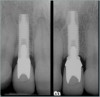

Figure 15  Initial periapical radiograph revealed internal root resorption of teeth Nos. 8 and 9 with almost complete horizontal severing of the crowns from the roots.

Figure 15